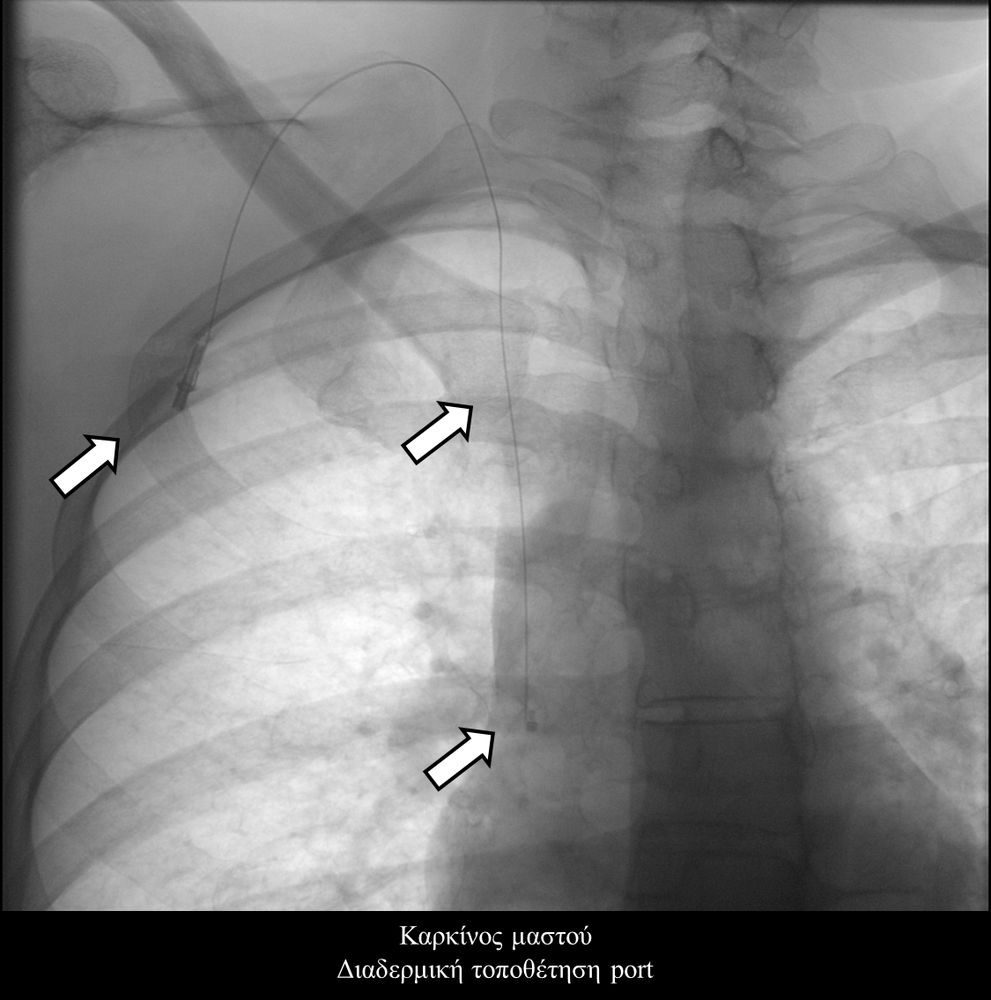

- Τα Port-a-Caths είναι εμφυτεύσιμοι κεντρικοί φλεβικοί καθετήρες με τύμπανο που τοποθετούνται διαδερμικά συνηθέστερα στο πρόσθιο θωρακικό τοίχωμα και ενώνονται μέσω υποδόριου τούνελ με την έσω σφαγίτιδα φλέβα. Η τοποθέτησή τους γίνεται στην αγγειογραφική σουίτα σε συνθήκες αποστείρωσης και με τη βοήθεια υπερηχογραφικού ελέγχου. Το Port-a-Cath είναι μια υποδόρια συσκευή, που δεν περιορίζει τις καθημερινές δραστηριότητεςκαι δεν απαιτεί συχνή φροντίδα. Ο ογκολογικός ασθενής μπορεί να κάνει άφοβα μπάνιο ακόμα και στη θάλασσα. Οι κίνδυνοι επιμόλυνσης και θρόμβωσης του καθετήρα είναι πολύ χαμηλοί, ενώ η διάρκεια χρήσης του μπορεί να ξεπεράσει και τα 5 έτη. Επιπλέον ενδείκνυται η χρήση τους σε αξονικούς και μαγνητικούς τομογράφους έως 1.5 Tesla.